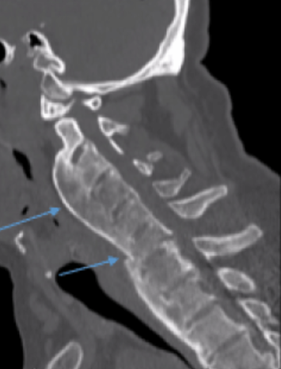

1) Ossification of the posterior longitudinal ligament (OPLL)

OPLL is present in approximately 50% of patients with cervical DISH and is most common in the cervical spine, representing 75% of all OPLL cases (2). OPLL may occur in the thoracic and lumbar spine as well. It is twice as common in men than women and slightly more common in Asian countries (3). Patients with OPLL may be asymptomatic or present with symptoms consistent with central canal stenosism such as radiculopathy and myelopathy. Cord injury from minor trauma is also a greater risk in those patients with OPLL, particularly in the cervical spine. CT imaging is the best imaging modality to assess the degree of central canal stenosis. Treatment may be conservative, but surgical treatment may be appropriate when neurologic symptoms are present. Great care and caution should be taken when assessing and treating your patients with OPLL.